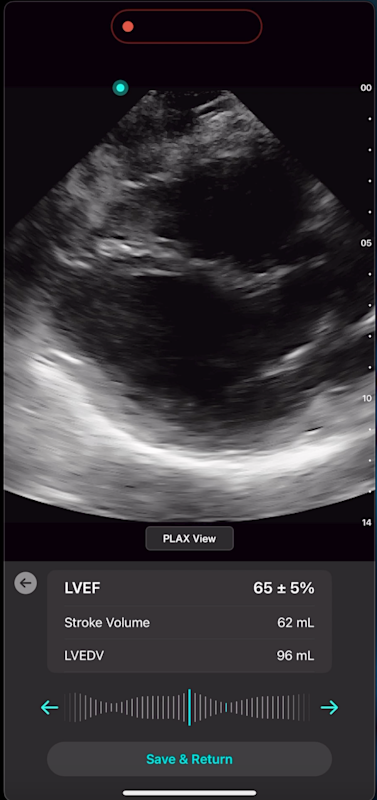

Cardiac AI

With Exo’s Cardiac AI, you can measure left ventricular ejection fraction (LVEF) and stroke volume in a few heartbeats in both parasternal long axis (PLAX) and apical four-chamber (A4C) views, making it easier than ever for POCUS users to get to answers.